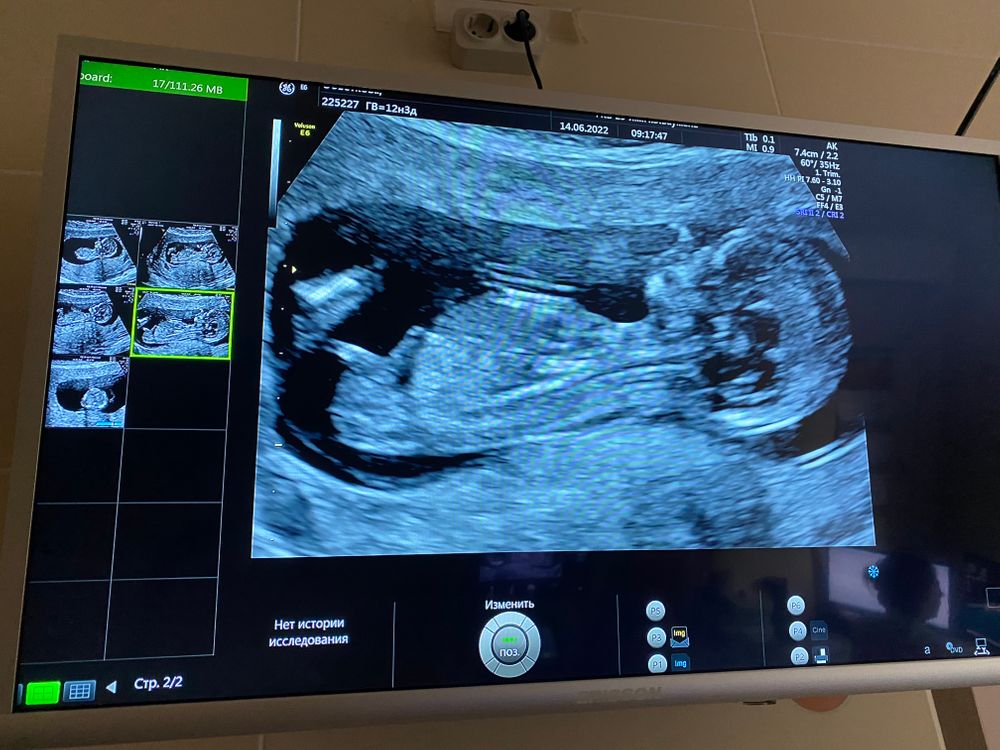

Всем приветик! Прошла я сегодня скрининг и хоть успокоилась😄а то с 8 недель не была на узи и было как то волнительно как там поживает малыш! По узи все соответствует сроку, твп 1.7, носовая кость определяется! Пол не сказала, смотрела смотрела и говорит не буду предполагать) говорит приходите через пару недель и точно скажу! Но я буду ждать 2 скрининг, который будет только 3 августа) односрочницы как вы себя чувствуете?)💐